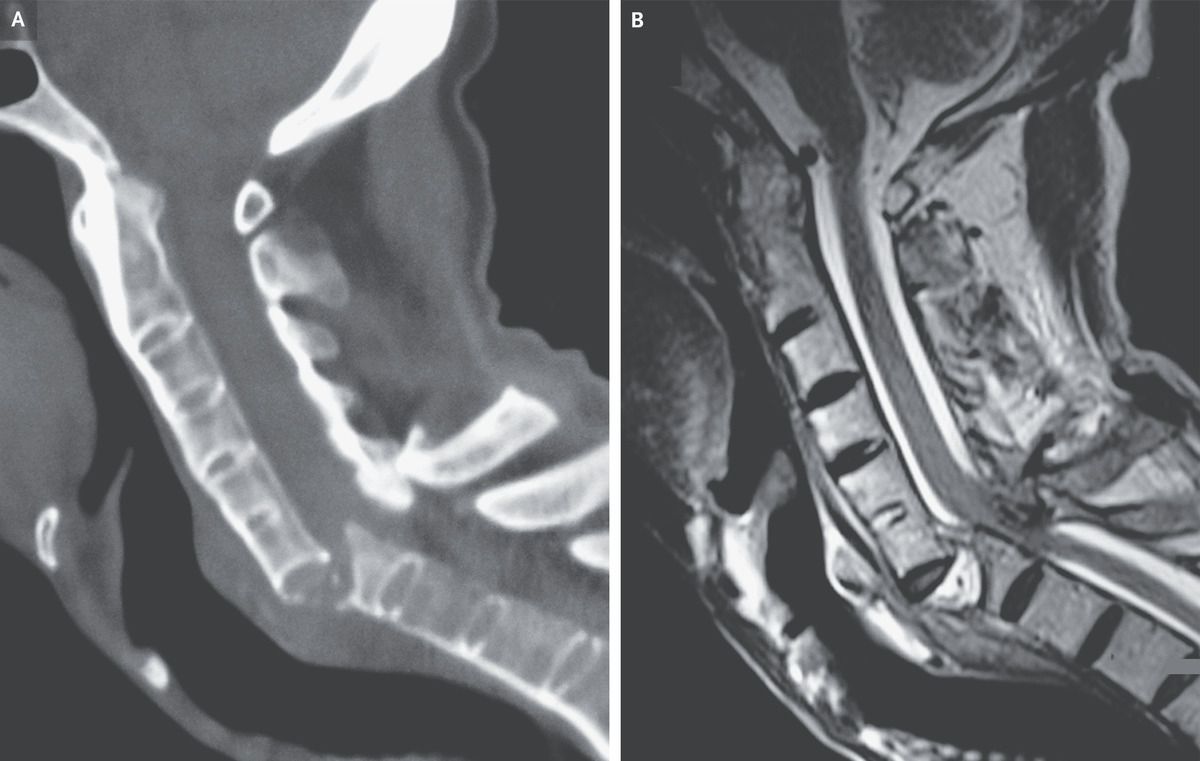

A 60-year-old man with a history of ankylosing spondylitis presented to the emergency department with neck pain and paralysis of the arms and legs after a fall. During the previous 5 years, he had not received treatment for the ankylosing spondylitis. At presentation, the blood pressure was 80/40 mm Hg and the heart rate was 56 beats per minute. Findings on physical examination were consistent with acute compression of the lower cervical spinal cord. Vasopressors were infused to treat neurogenic shock, and bladder catheterization was performed to treat acute urinary retention. Computed tomography of the cervical spine showed fused vertebrae with a displaced fracture — also known as a chalk-stick fracture — at the level of C6–C7 (Panel A). Magnetic resonance imaging of the cervical spine confirmed spinal cord compression at that level (Panel B). Ankylosis of the vertebrae results in increased bone fragility and risk of pathologic fracture. Neck or back pain after even minor trauma should prompt cross-sectional imaging to evaluate for serious injury. Surgical decompression and fusion of the spine were performed. Postoperatively, the patient regained function of his upper limbs but died from pneumonia 5 weeks later.